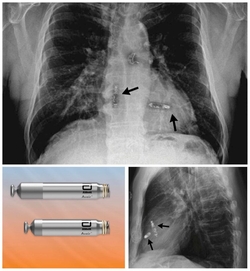

The leadless pacemaker is inserted through a catheter, with no wires or visible scarring, from the top of the leg in the groin region through the skin.

Two small 'bullet-sized' devices are placed in each chamber, syncing together wirelessly using electrical impulses.